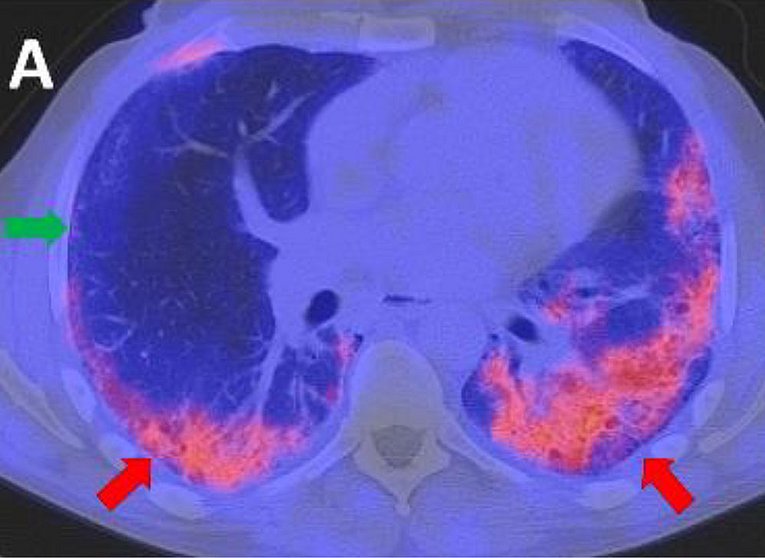

The red arrows show fibrotic areas of the left and right lower lobes of the lung in a person with systemic sclerosis.

The green arrow shows non-fibrotic areas in the middle lobe.

Source: Uni-Klinikum Erlangen